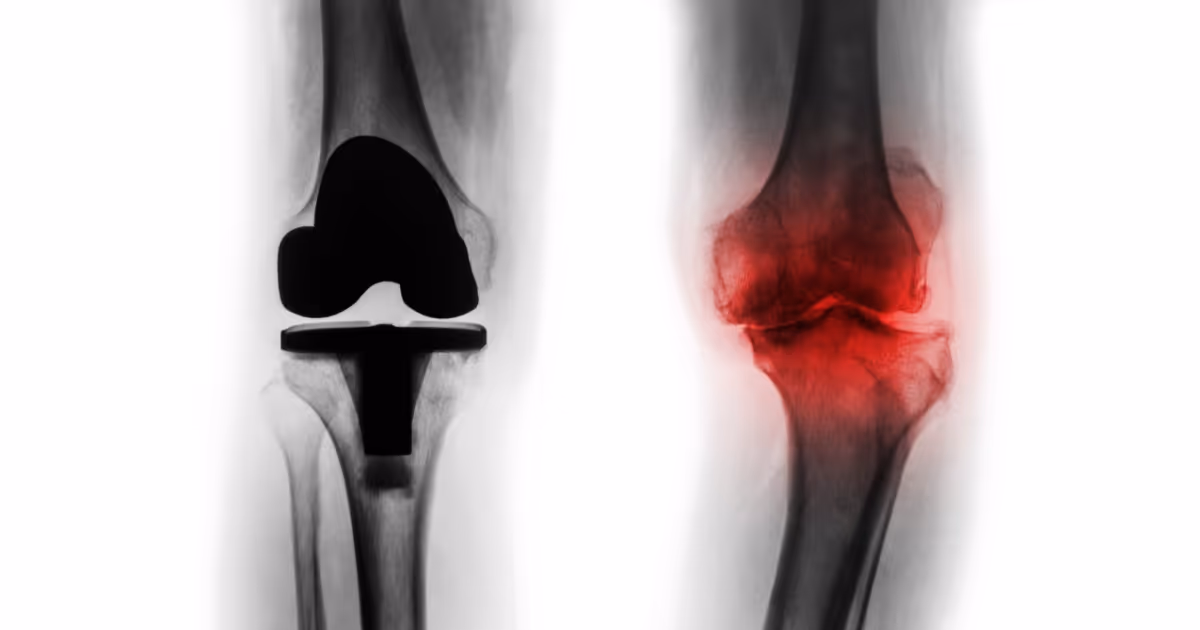

(ซ้าย) ข้อเข่าเทียมทั้งข้อ (ขวา) โรคข้อเข่าเสื่อมระยะรุนแรง

- ผ่าตัดเปลี่ยนข้อเข่าเทียมทั้งข้อ (Total knee replacement: TKA) เป็นการผ่าตัดเปลี่ยนข้อเข่าเทียมทั้งหมด เพื่อรักษาโรคข้อเข่าเสื่อมรุนแรง กระดูกอ่อนผิวข้อสึกกร่อนทั่วทั้งข้อ กระดูกเสียดสีกันมาก เข่าโก่งผิดรูป มีกระดูกงอกรอบข้อ ข้อติดขัดจนขยับลำบาก โดยแพทย์จะผ่าตัดใส่ข้อเข่าเทียมเข้าไปคลุมผิวข้อเข่าเสื่อมทั้งหมด ทั้งด้านบน (กระดูกต้นขา) ด้านล่าง (กระดูกหน้าแข้ง) และอาจรวมถึงผิวข้อสะบ้า เพื่อลดอาการการปวด และช่วยให้สามารถกลับมาใช้งานข้อเข่าได้อย่างมั่นคง